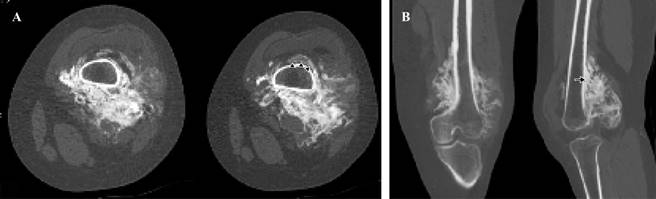

Computerized Tomography showed a juxtacortical and heterogeneous tumor on the posterior surface of the femur There were hypodense and hyperdense areas. The bone marrow was not involved (Figure 2).

Figure 2: Computerized Tomography. Axial cut (A), Multiplanar reconstruction (B). Presence of juxtacortical tumor on the posterior surface of the metaphysis and distal third of femoral diaphysis, showing abundant ossification, which surrounds almost the entire circumference of the femur, identifying the sign of the rope (arrowheads) and cortical thickening (arrow). The bone marrow is respected.